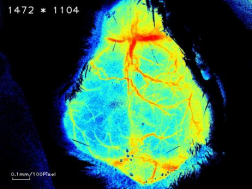

④活体脑部血流监测:激光多普勒或激光散斑成像技术可监测脑部血管血流动态变化,通过卒中前后血管血流的变化可以判断脑部血管梗塞情况(如图2所示),进而可评估模型的成功性以及药物干预的效果。

正常鼠 MCAO鼠

图2:正常组和MCAO模型组小鼠脑部血流成像对比图(佳维斯实验数据)